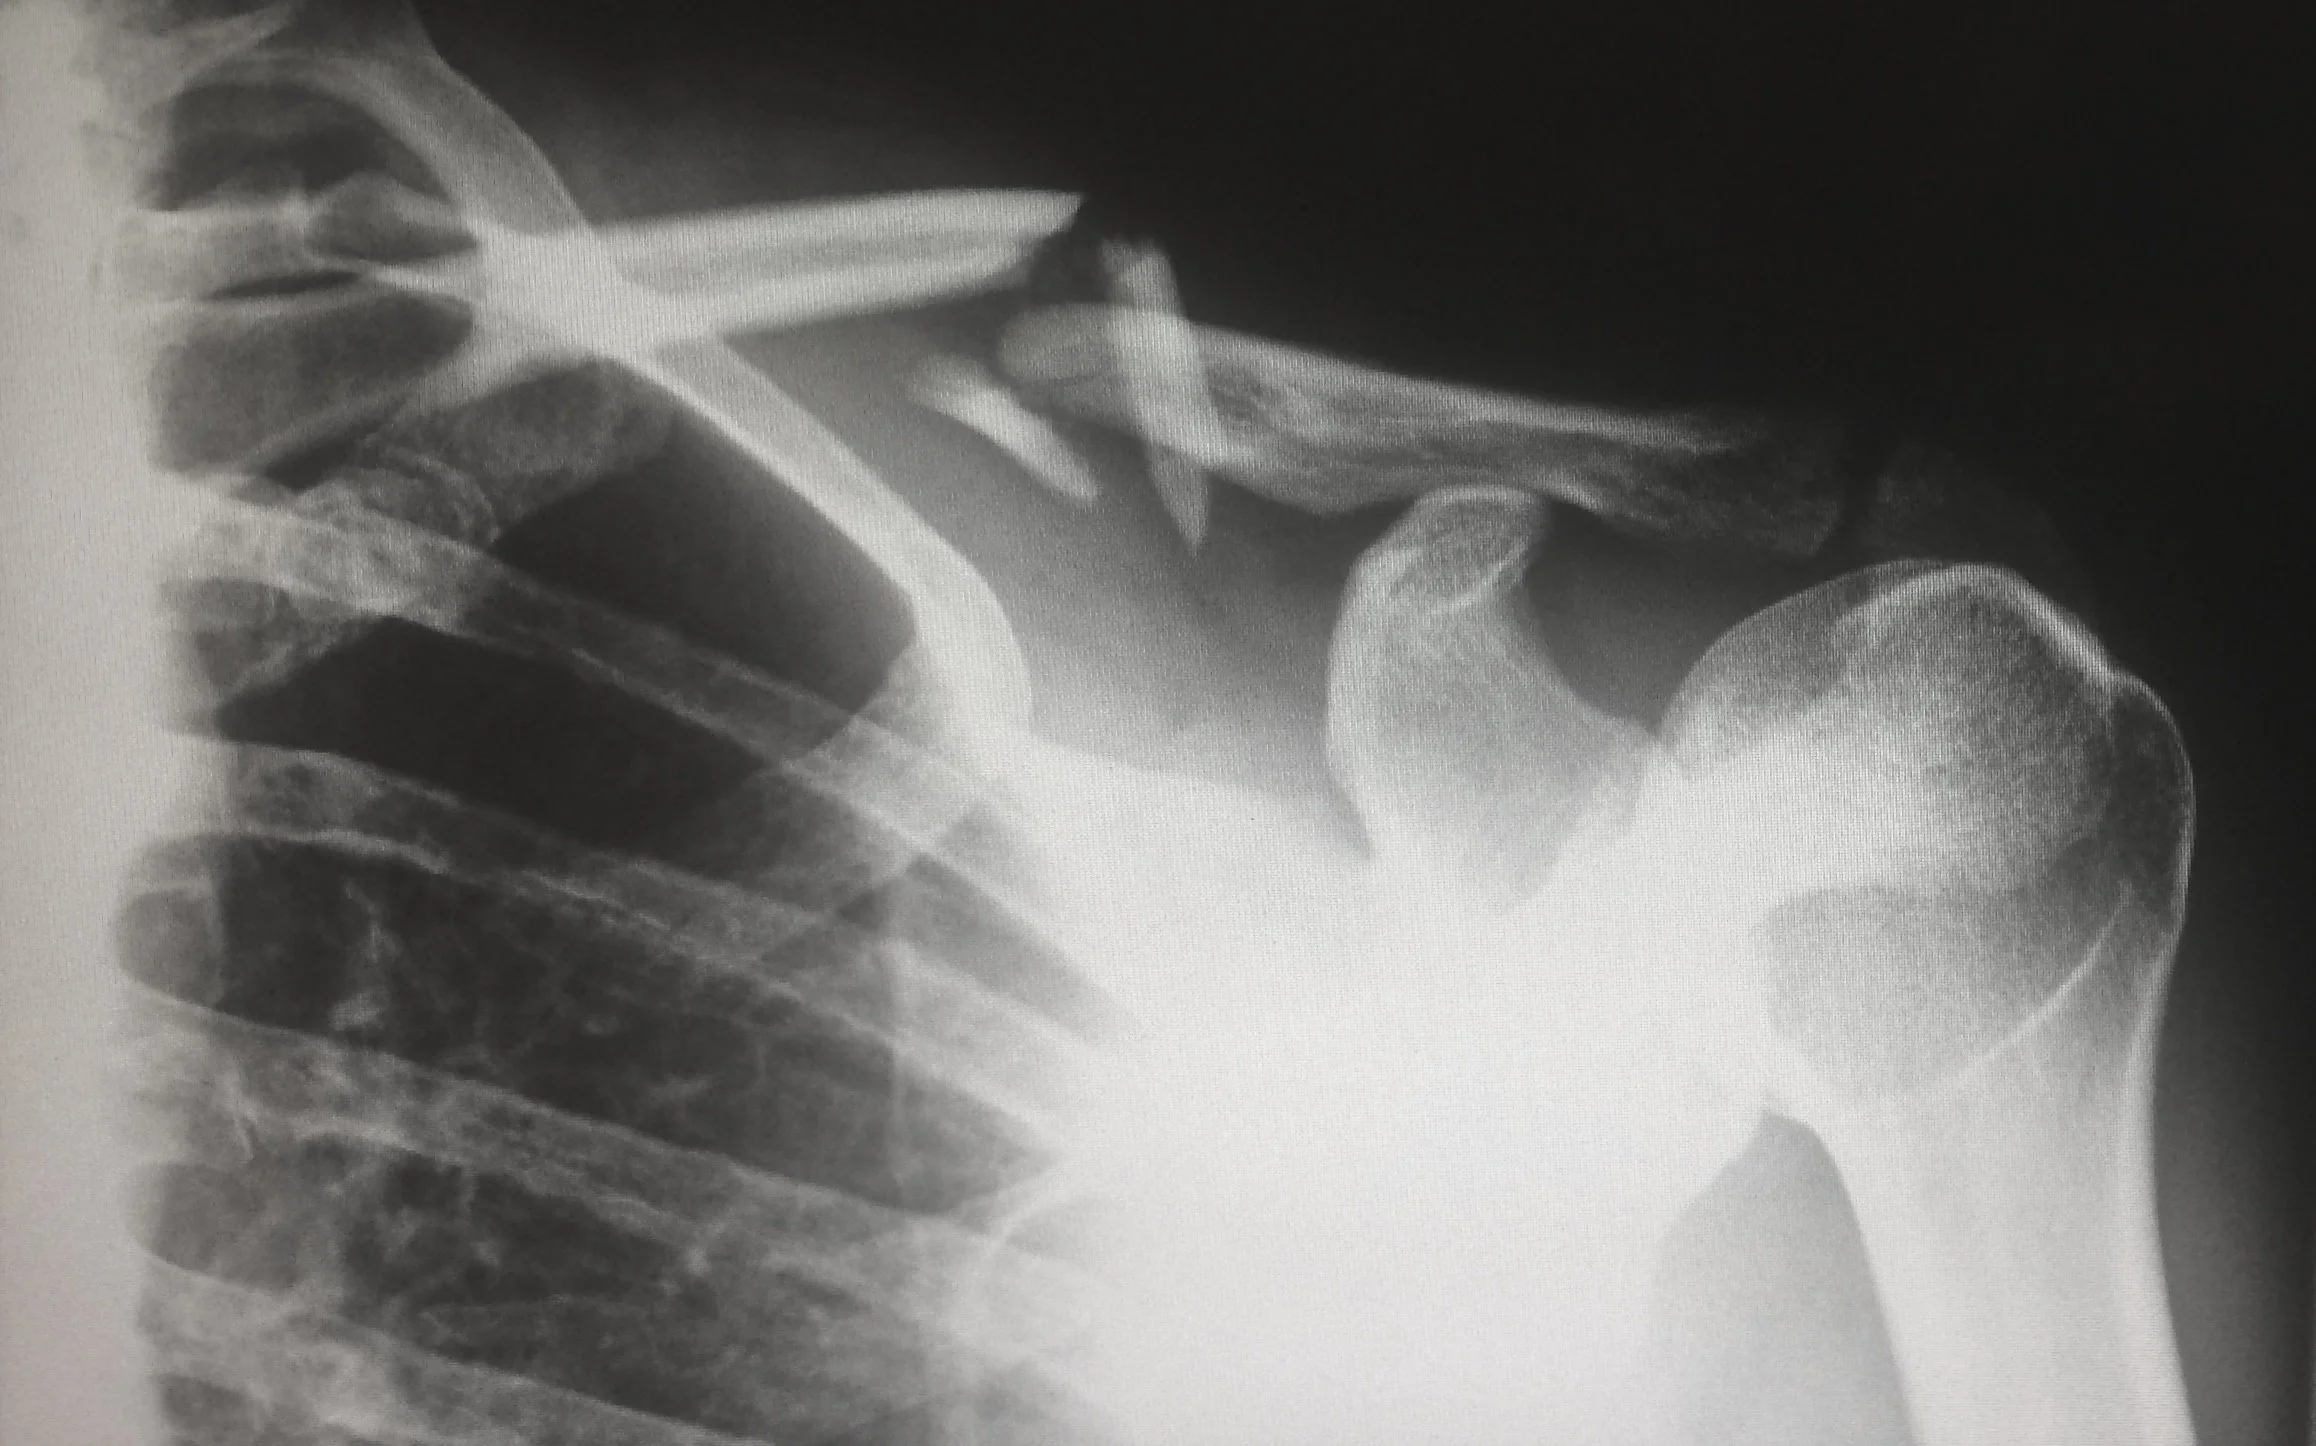

X-ray of a clavicle fracture

X-ray of the left shoulder showing a midshaft (middle) clavicle fracture.